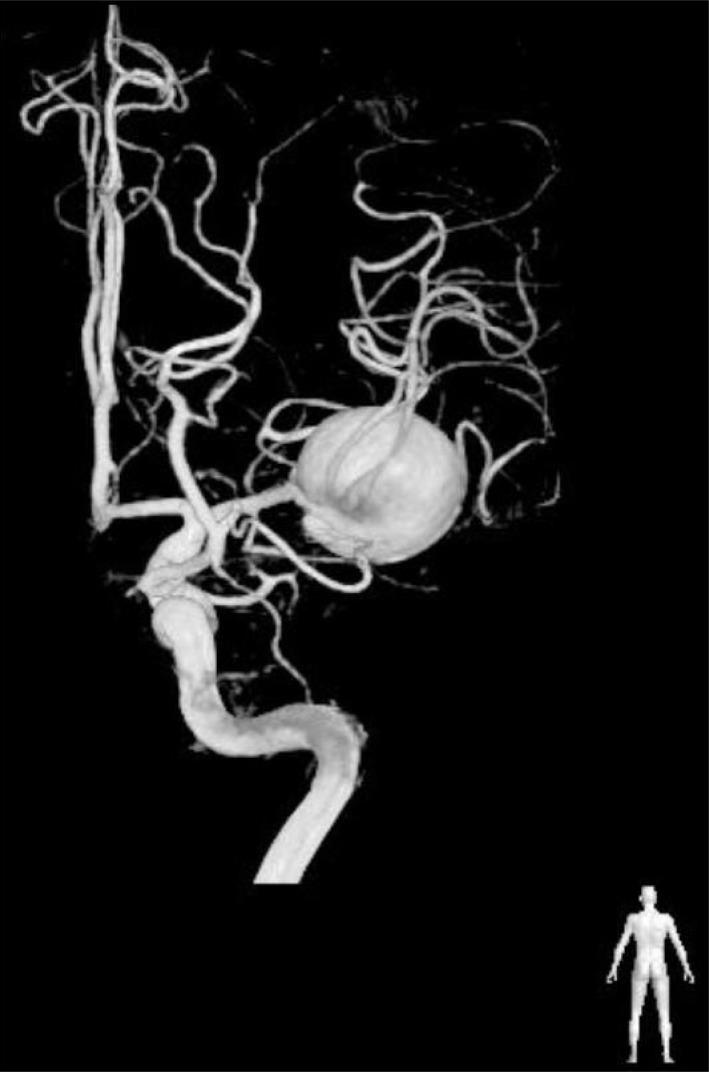

There are few observation papers regarding the natural history of an aneurysm. We report on a case of a completely occluded middle cerebral artery (MCA) aneurysm. A 47-year-old female patient presented with a headache and was diagnosed with rupture of a right MCA aneurysm. Due to a high risk of direct neck clipping, she received conservative treatment after craniotomy and wrapping of her aneurysm. The patient's condition showed improvement, with complete occlusion of the aneurysm and considerable reduction of the aneurysm in size after approximately three years. This is a rare case of an aneurysm of MCA that showed spontaneous resolution. Finally, on the angiogram, characteristics of an aneurysm to occlude spontaneously will be presumed based on literature reviews.

关于动脉瘤自然史的观察性论文很少。我们报告一例大脑中动脉(MCA)动脉瘤完全闭塞的病例。一名47岁女性患者因头痛就诊,被诊断为右侧MCA动脉瘤破裂。由于直接夹闭颈部的风险较高,她在开颅手术和包裹动脉瘤后接受了保守治疗。大约三年后,患者病情有所改善,动脉瘤完全闭塞且大小显著缩小。这是一例罕见的MCA动脉瘤自发消退病例。最后,基于文献综述,在血管造影上推测动脉瘤自发闭塞的特征。